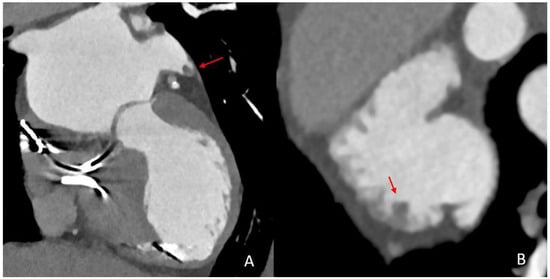

- Larsen, N.; Austein, F.; Klintz, T.; Campbell, G.; Sedaghat, S.; Aludin, S.; Schunk, D.; Both, M.; Jansen, O.; Langguth, P. Spectral cardiac CT in acute stroke patients. Sci. Rep. 2023, 13, 6781. [Google Scholar] [CrossRef]

- Austein, F.; Eden, M.; Engel, J.; Lebenatus, A.; Larsen, N.; Both, M.; Piesch, T.C.; Salehi Ravesh, M.; Meyne, J.; Jansen, O.; et al. Practicability and Diagnostic Yield of One-Stop Stroke CT with Delayed-Phase Cardiac CT in Detecting Major Cardioembolic Sources of Acute Ischemic Stroke: A Proof of Concept Study. Clin. Neuroradiol. 2021, 31, 911–920. [Google Scholar] [CrossRef]

- Hur, J.; Kim, Y.J.; Lee, H.-J.; Nam, J.E.; Hong, Y.J.; Kim, H.Y.; Lee, J.W.; Choi, B.W. Cardioembolic stroke: Dual-energy cardiac CT for differentiation of left atrial appendage thrombus and circulatory stasis. Radiology 2012, 263, 688–695. [Google Scholar] [CrossRef] [PubMed]

- Teunissen, C.; Habets, J.; Velthuis, B.K.; Cramer, M.J.; Loh, P. Double-contrast, single-phase computed tomography angiography for ruling out left atrial appendage thrombus prior to atrial fibrillation ablation. Int. J. Cardiovasc. Imaging 2017, 33, 121–128. [Google Scholar] [CrossRef] [PubMed]

- Liu, X.-W.; Yan, L.-Q.; Wang, G.-S.; Sun, Y.-H.; Bao, W.-J.; Zhang, H.-W.; Yang, L.; Chen, C.; Li, M.-Y.; Yang, L.; et al. Left atrial appendage filling defects restricted to the early phase of cardiac computed tomography is significantly associated with ischemic stroke. Clin. Imaging 2023, 98, 16–21. [Google Scholar] [CrossRef] [PubMed]